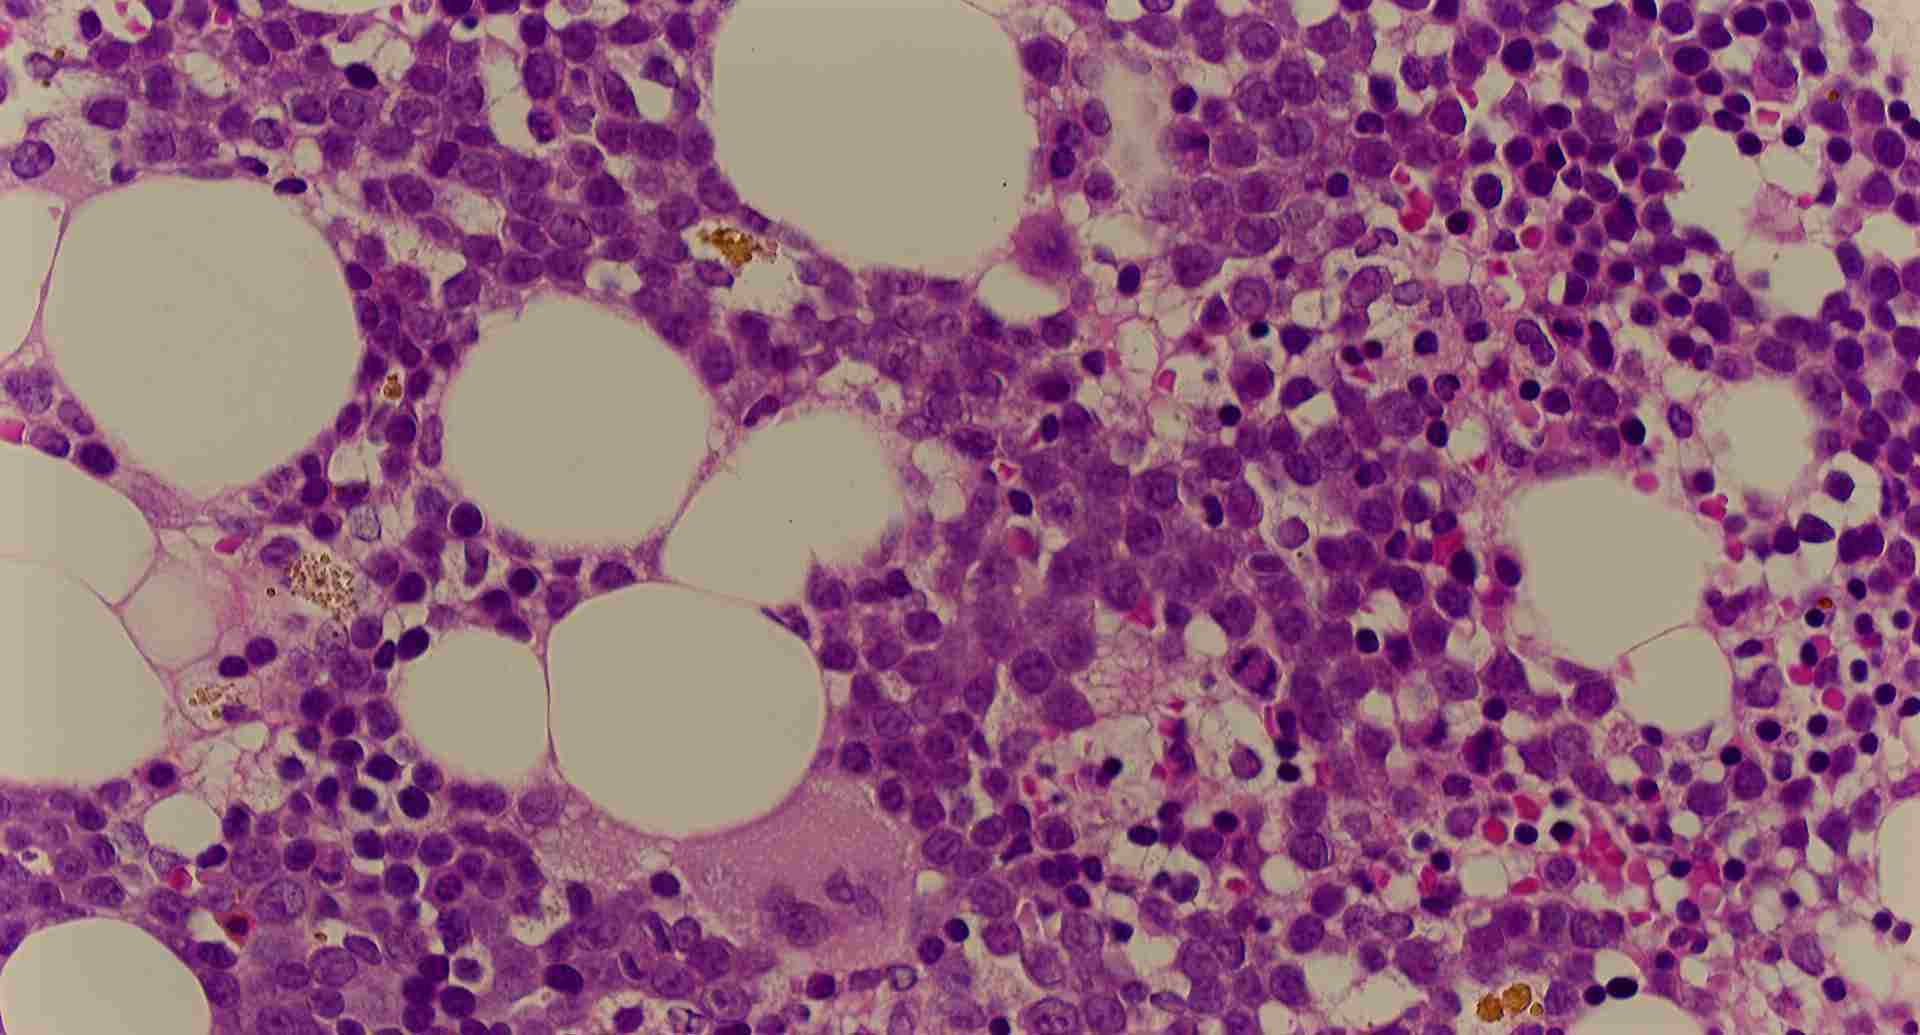

標本2

標本2の説明